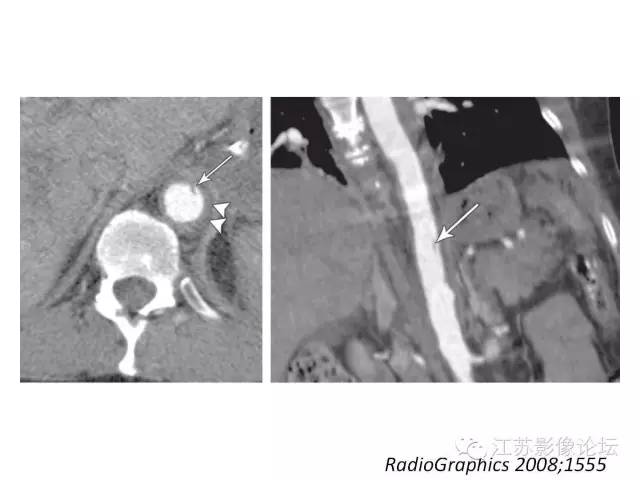

在主动脉夹层鉴别真假腔至关重要,一系列CT表现如“beak sign鸟嘴征”,主动脉“cobwebs蜘蛛网”,这样的表述有着明确的鉴别意义。平扫CT的价值,特别是用于壁间血肿的诊断也加以论述。各种临床和影像学表现共同类似主动脉综合症的情况也是很常见。